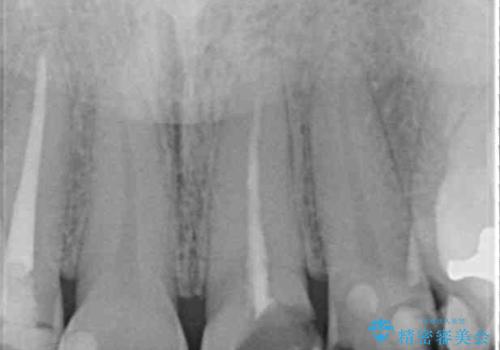

神経が除去されている歯、根管治療の必要な歯、むし歯の非常に大きな歯に対してオールセラミッククラウンにて補綴治療を行うこととしました。

左上の欠損部はインプラントを埋入した上で補綴することとしました。

インプラント部は治癒待ちの期間が長くなるため、その期間を利用して下顎の叢生を解消し、より理想的な咬み合わせで補綴治療を行うこととしました。